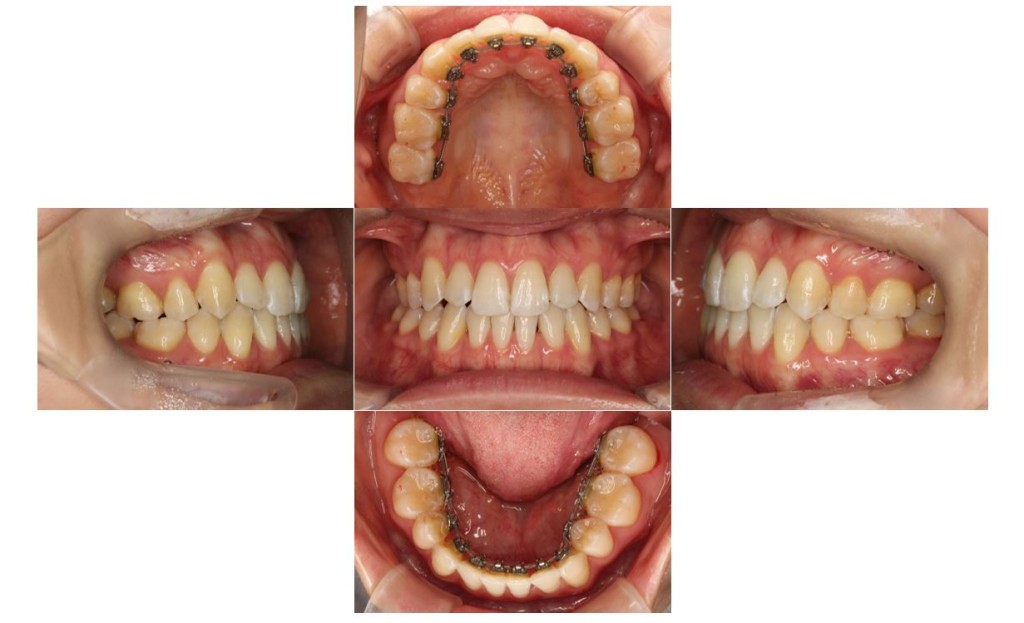

当院の症例

| 主訴 | 下の歯が、上の歯より前に出ていて顎が出ているのが気になる。受け口を治したい。でこぼこもあり歯磨きにしくいので、虫歯予防のためにも綺麗に並べたい。 |

| 治療期間 | 2年2ヶ月(29回) |

| 抜歯 | 有(左上4、左下5、上下親知らず4本) |

| 矯正の装置 | 裏側矯正(舌側矯正) |